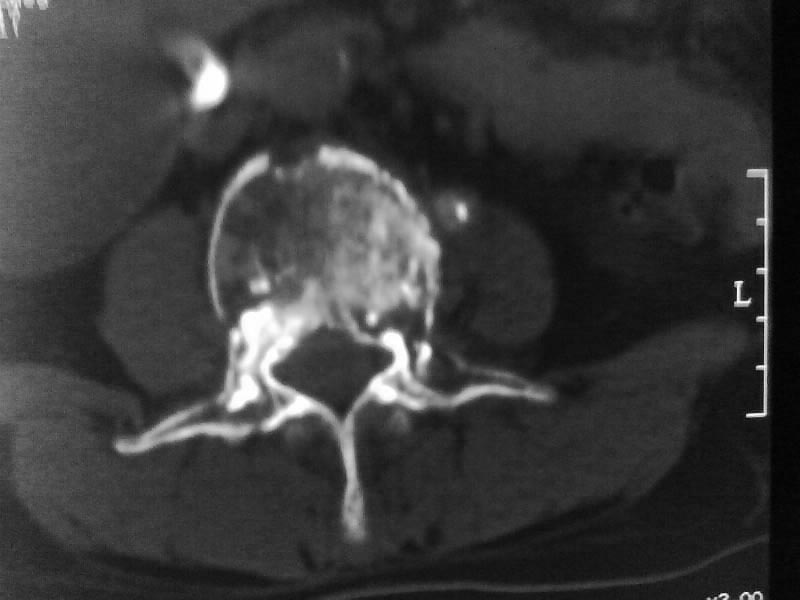

定位相示l2呈楔形改变(ct示陈旧性骨折改变,图像未传),l4.5椎体融合,以下是l4.5ct平扫.请各位看看,

考虑结核(有破坏、硬化及死骨)。

1、三四椎体结核,2、水平骶椎。

1、l1压缩性骨折(陈旧性)。

2、l3、4椎体结核。

就是腰1压缩性骨折,腰3\\4椎体结核(融合),水平骶椎.

支持 l1椎体陈旧性压缩性骨折;l3、4椎体结核(融合);水平骶椎。